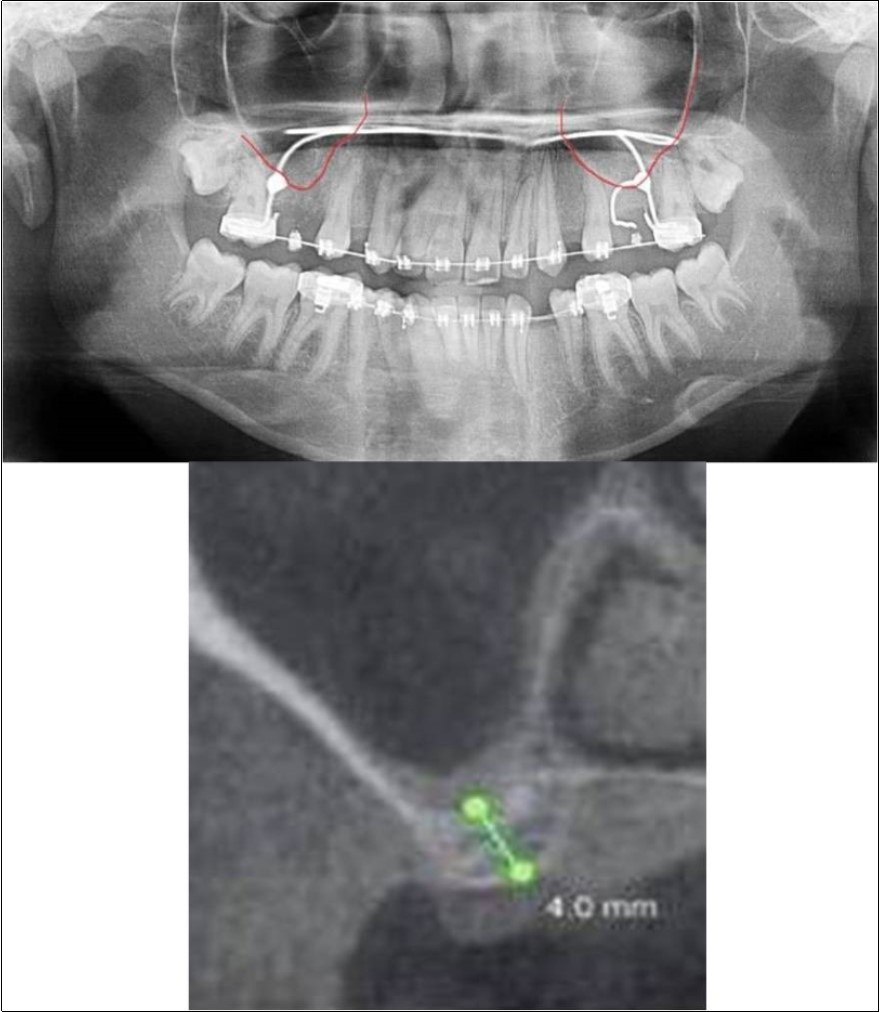

A 19 years old young female patient reported to the Department of Oral and Maxillofacial Surgery, D.A.P.M.R.V Dental College and Hospital seeking options for replacement of her missing right and left upper first molars with a fixed prosthesis as she was uncomfortable with the removable partial denture i.r.t 16 and 26. The teeth were extracted 6 months ago because of gross loss of crown structure and poor prognosis for root canal treatment. Patient was also undergoing fixed orthodontic treatment for proclined upper anteriors. Patient did not give history of any existing sinus pathologies. All possible rehabilitative options were explained to the patient and a treatment plan of replacement of missing teeth with implant supported prosthesis using two dental implants was finalized.

Clinical and Radiological Assessment:

1.Partially edentulous maxillary arch with missing 16 and 26;

2.Increased pneumatisation of right and left maxillary sinus;

3.Height of available bone-

16 region: 6.5mm;

26 region: 6.2mm;

4.Transverse thickness of available bone (CBCT evaluation)-

16 region: 8.3mm;

26 region: 10.5mm;

5.Fixed orthodontic appliance;

6.Inter-ridge space adequate to place implant (11mm).

Treatment:

Patient underwent the procedure of indirect sinus elevation using sinus osteotomes in relation to 26 region. Calcium phosphosilicate putty was dispensed as the graft material through the crestal osteotomy site to maintain the elevated sinus membrane followed by placement of 5 x 10mm dental implant under local anaesthesia and strict aseptic protocols. The implant was allowed to osseo-integrate for a period of six months during which the patient was followed-up periodically and was assessed for peri-implantitis, crestal bone loss and mobility. Patient was taken-up for direct sinus elevation via lateral window approach for sinus augmentation i.r.t 16 region. Under aseptic conditions and local anaesthesia, lateral wall of maxilla was exposed after muco-periosteal flap elevation. A window was created of 1cm diameter corresponding to apical aspect of 16. Sinus membrane was identified and elevated using sinus elevators and reamers without perforating the lining. Once the sinus membrane was elevated, phosphosilicate putty was dispensed through the lateral osteotomy site as the graft material to achieve an augmentation of 1cm assessed clinically and confirmed using post-operative OPG. At the end of 6 months, a repeat CBCT scan was advised to evaluate the increase in bone height. (Figure 13a,b, pre-treatment; Figure 14a,b, post-treatment)

Figure 13.(a,b) Pre-treatment OPG and cross section of CBCT showing residual alveolar bone height for Case No.4;